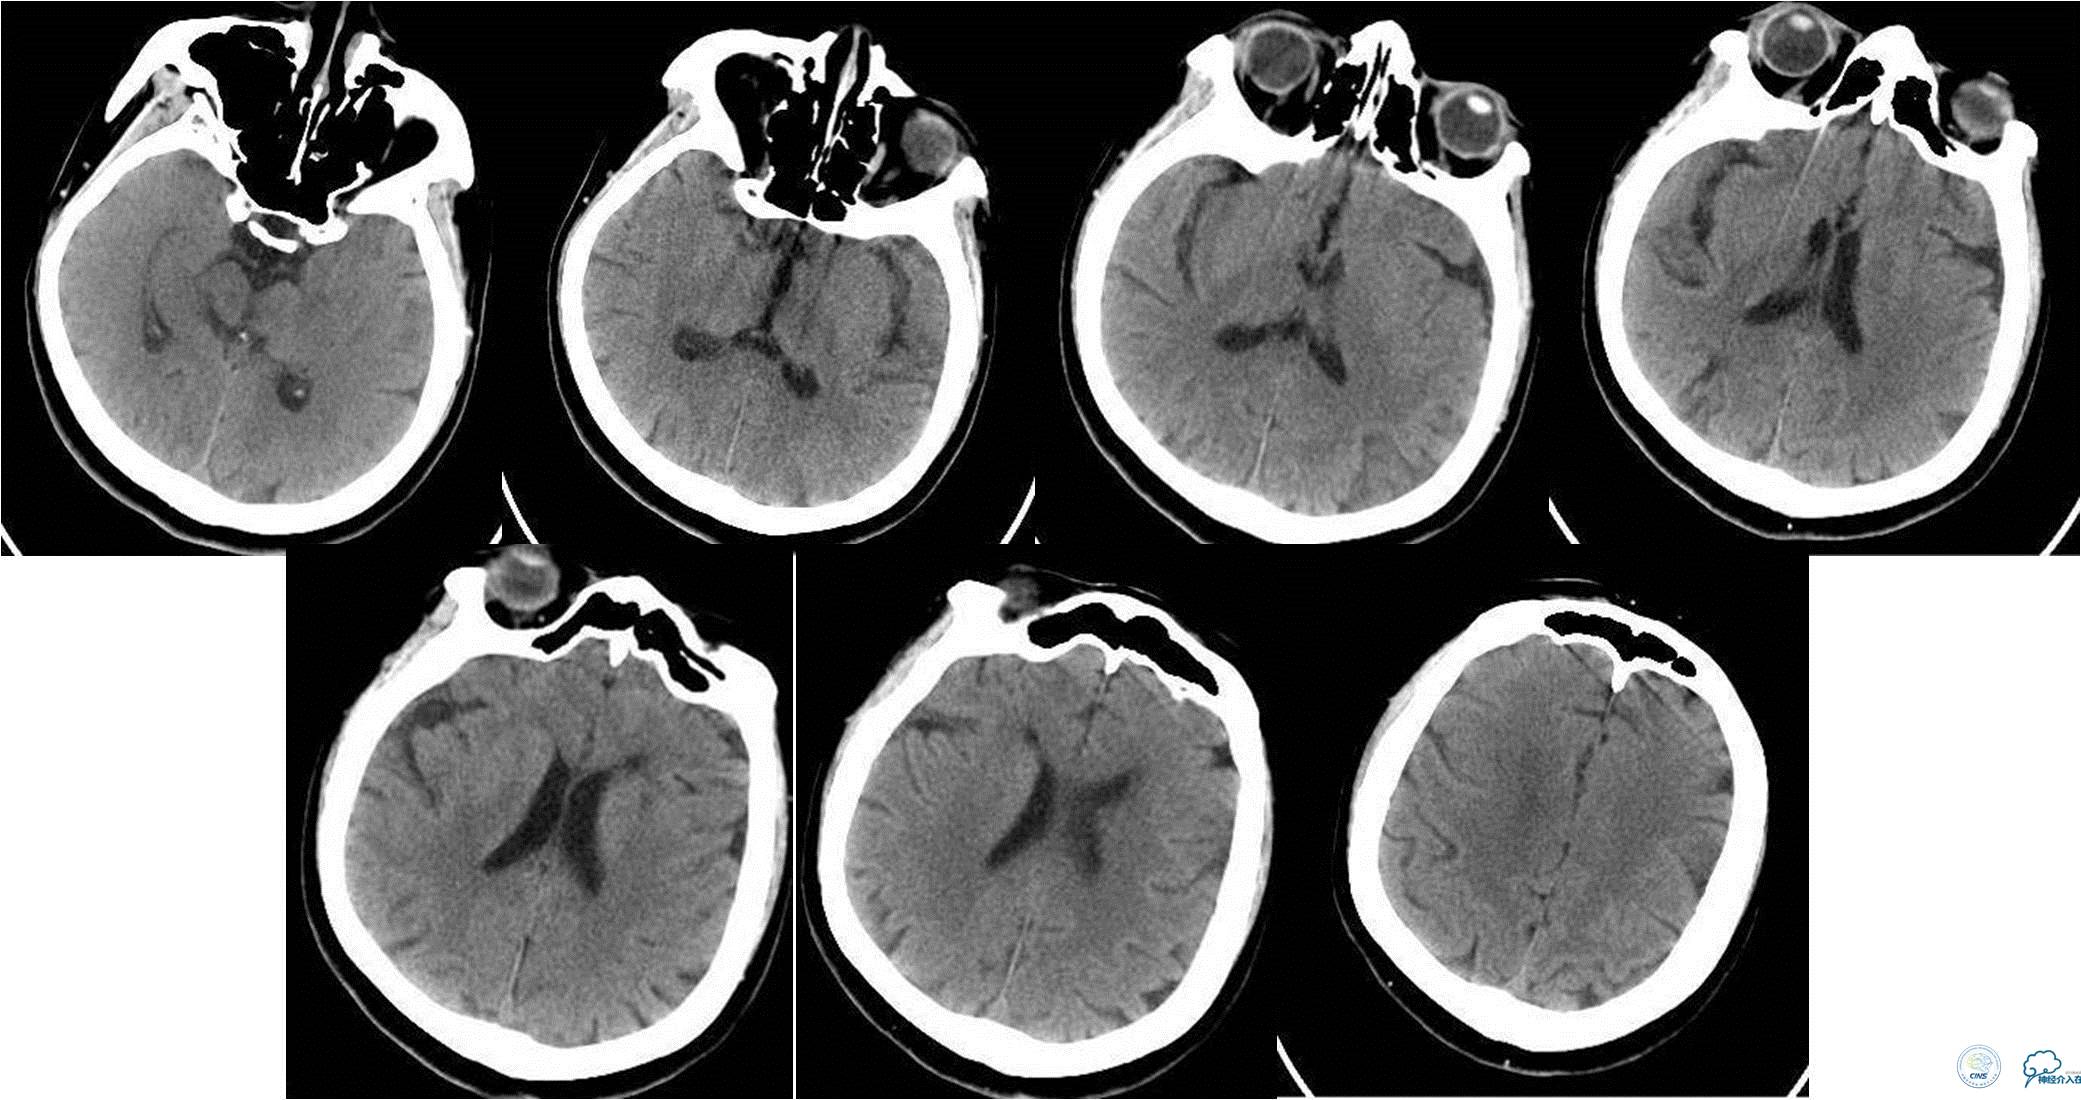

入院时急查颅脑CT(发病2.5小时)

入院时颅脑CTA(发病4小时)